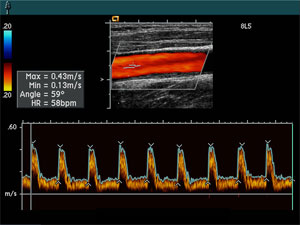

IMT stands for Intimal Medial Thickness. This is the technical way to refer to the thickness of your blood vessel walls. Measuring the IMT is a way to measure atherosclerosis, which is a disease of the vascular system. The progression of this disease leads to cardiovascular and cerebrovascular complications such as heart attack and stroke.

For this reason, tracking and analyzing a patient’s level of atherosclerosis provides invaluable insight into a person’s cardiovascular Heart. Because the IMT of the common carotid artery (located in the neck) is the most accurate indicator of a patient’s system wide atherosclerosis, this is the location that IMT testing is performed.